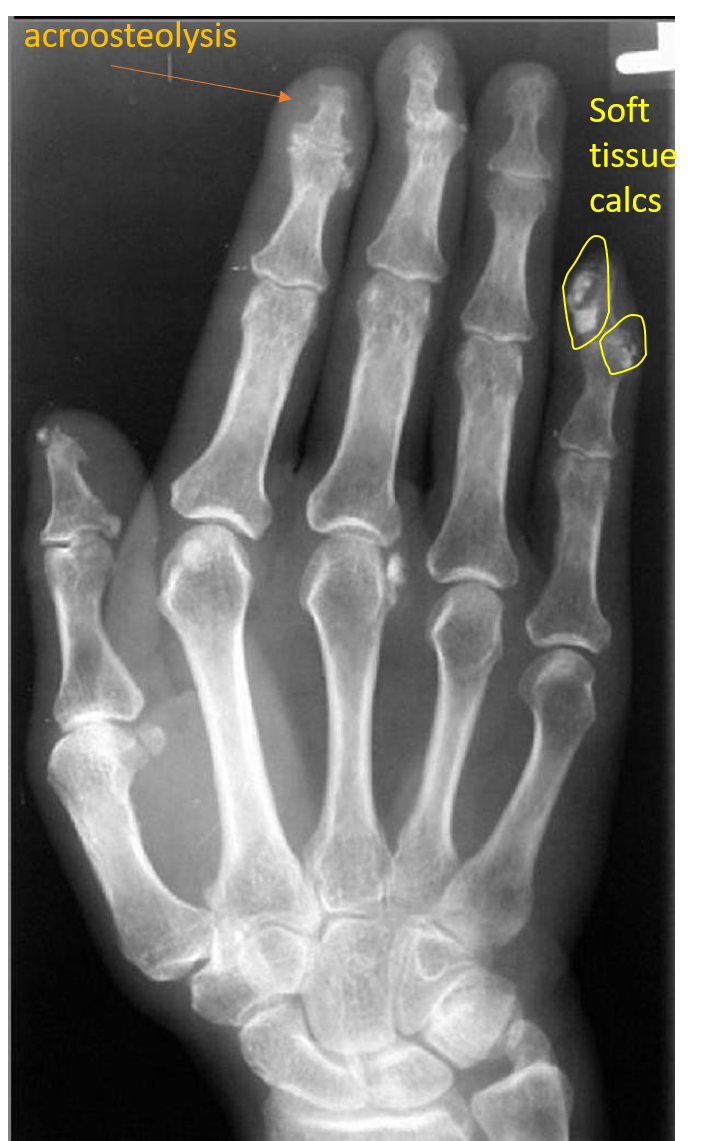

dystrophic soft tissue calcs plus acroosteolysis

scleroderma

Acroosteolysis differential

Acroosteolysis and dystrophic soft tissue calcs

acroosteolysis diff

scleroderma ** neuropathy polyvinyl chloride exposure thermal injury hyperparathyroidism Hajdu-Cheney